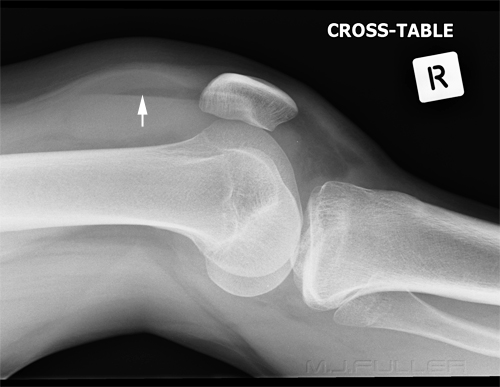

Horizontal Beam Lateral

Lipohaemarthrosis